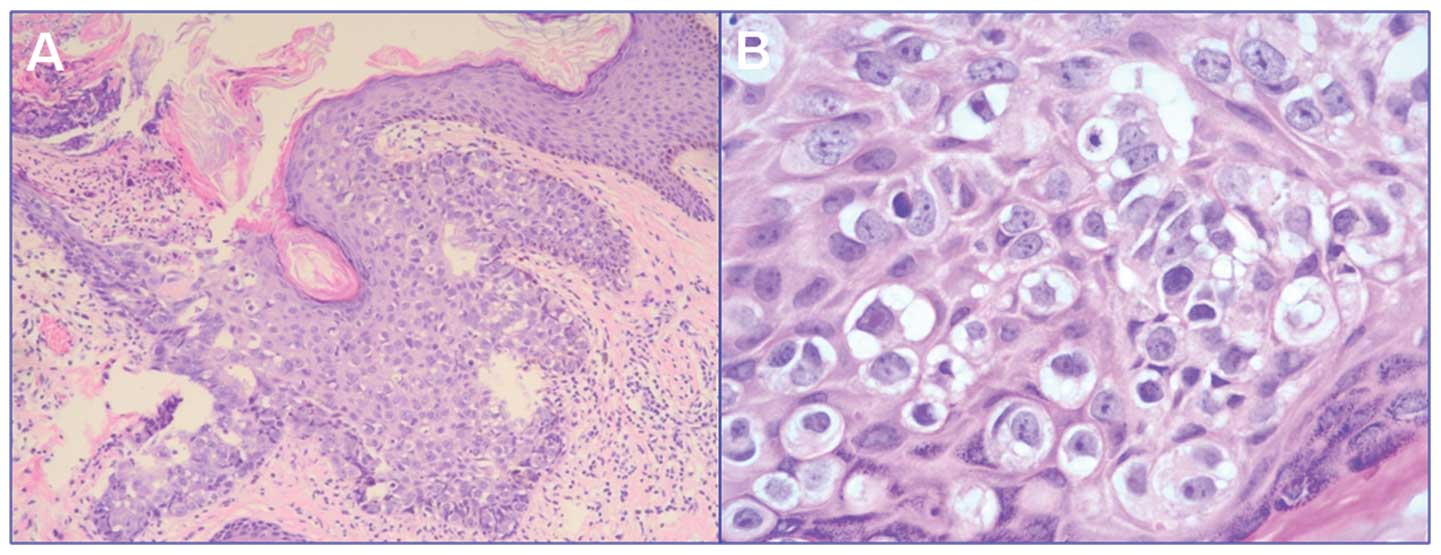

Исследование: микропрепарат молочной железы в медицине

Раздел: Снимки-откровения